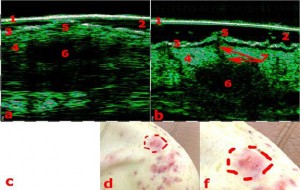

-Διαφοροποίηση μεταξύ υπερτροφικών και χηλοειδών ουλών

-Διάγνωση μορφών ακμής